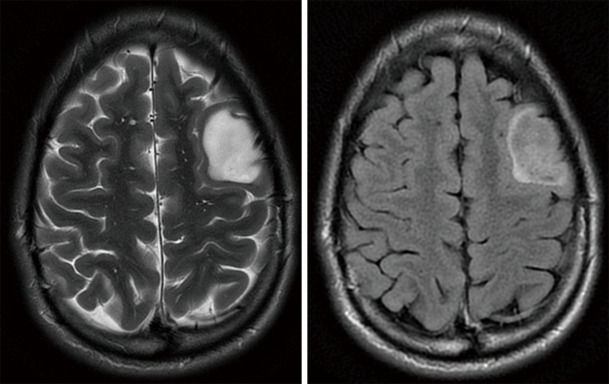

Abstract Image